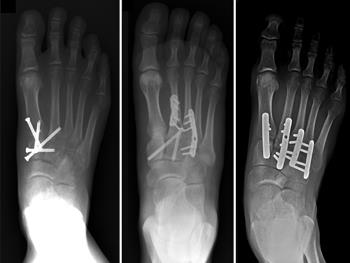

LISFRANC INJURY is basically known as fracture dislocation of tarsal and metatarsal joint complex which includes tarsal bones articulating with cuneiform cuboid.

In a Lisfranc joint injury there is usually damage to the cartilage covering these bones. The Lisfranc joint is the spot on top of your foot where the metatarsal bones the bridges to your toes connect to the rest of your foot. A Lisfranc fracture is a type of broken foot.

Lisfranc Injury any fracture or dislocation of the tarsal-metatarsal joint. Martin 1790-1847 a French surgeon and gynaecologist who first described the injury in 1815. Ad Medical-grade braces and supports shipped fast to your home.

Injury to 2nd metatarsal often results in dislocation of the other MTs. In the middle region of your foot midfoot a cluster of small bones form an arch. Lisfranc ligament attaches 2nd metatarsal to medial cuneiform.

Swelling is generally detected in the midfoot area on physical examination. The metatarsals dislocate from their normal articulation with the mid-tarsal bones. Dorsalis pedis may be injured in severe dislocation.